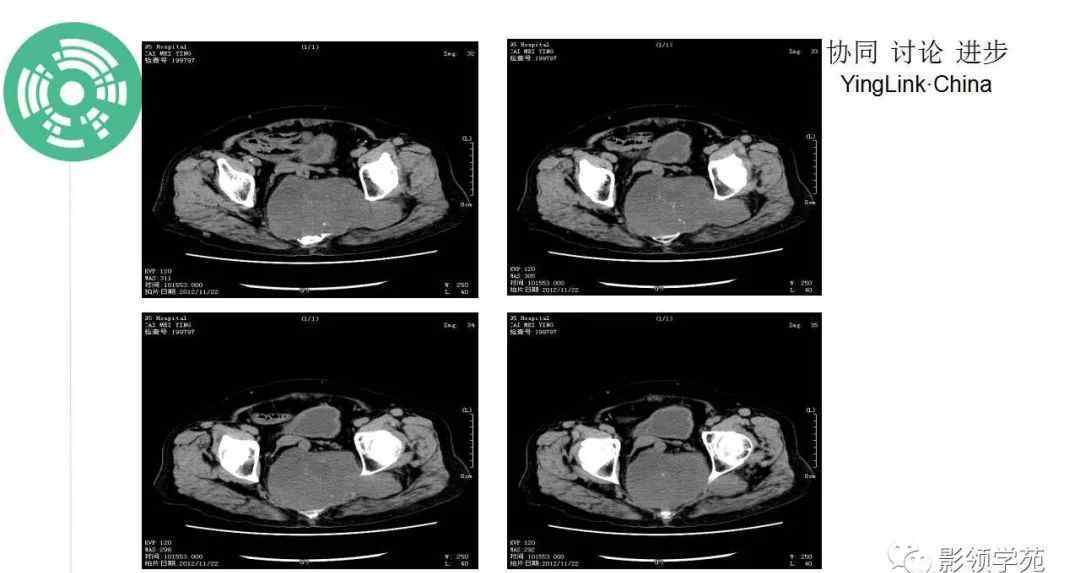

CT:一般表现为溶骨性膨胀性骨质破坏,常伴有软组织肿块,穿插斑片状钙化(钙化率低于软骨肉瘤),少数边缘表现为骨质硬化。